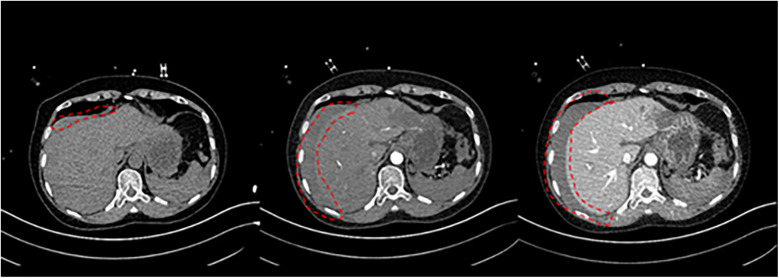

Postoperative pulmonary embolism (PE) poses a serious threat to a patient's life. However, cases involving concurrent liver rupture are exceedingly rare. This report describes a case of a patient who experienced cardiac arrest due to PE following lower extremity varicose vein surgery, followed by liver rupture during cardiopulmonary resuscitation (CPR). Under the timely intervention of a multidisciplinary team (MDT), the patient underwent extracorporeal membrane oxygenation (ECMO)-assisted resuscitation and hepatic repair surgery. Through a staged anticoagulation strategy, a balance was achieved between bleeding control and thrombosis prevention. Ultimately, after 23 days of treatment, the patient regained consciousness and was transferred to rehabilitation.